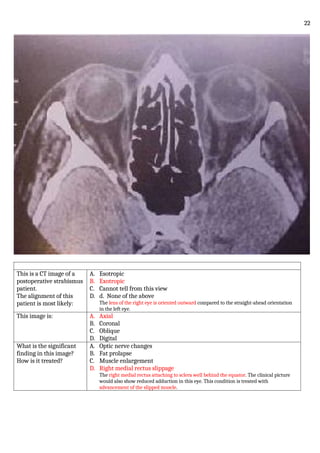

This is a CT image of a

postoperative strabismus

patient.

The alignment of this

patient is most likely:

A. Esotropic

B. Exotropic

C. Cannot tell from this view

D. d. None of the above

The lens of the right eye is oriented outward compared to the straight-ahead orientation

in the left eye.

This image is: A. Axial

B. Coronal

C. Oblique

D. Digital

What is the significant

finding in this image?

How is it treated?

A. Optic nerve changes

B. Fat prolapse

C. Muscle enlargement

D. Right medial rectus slippage

The right medial rectus attaching to sclera well behind the equator. The clinical picture

would also show reduced adduction in this eye. This condition is treated with

advancement of the slipped muscle.